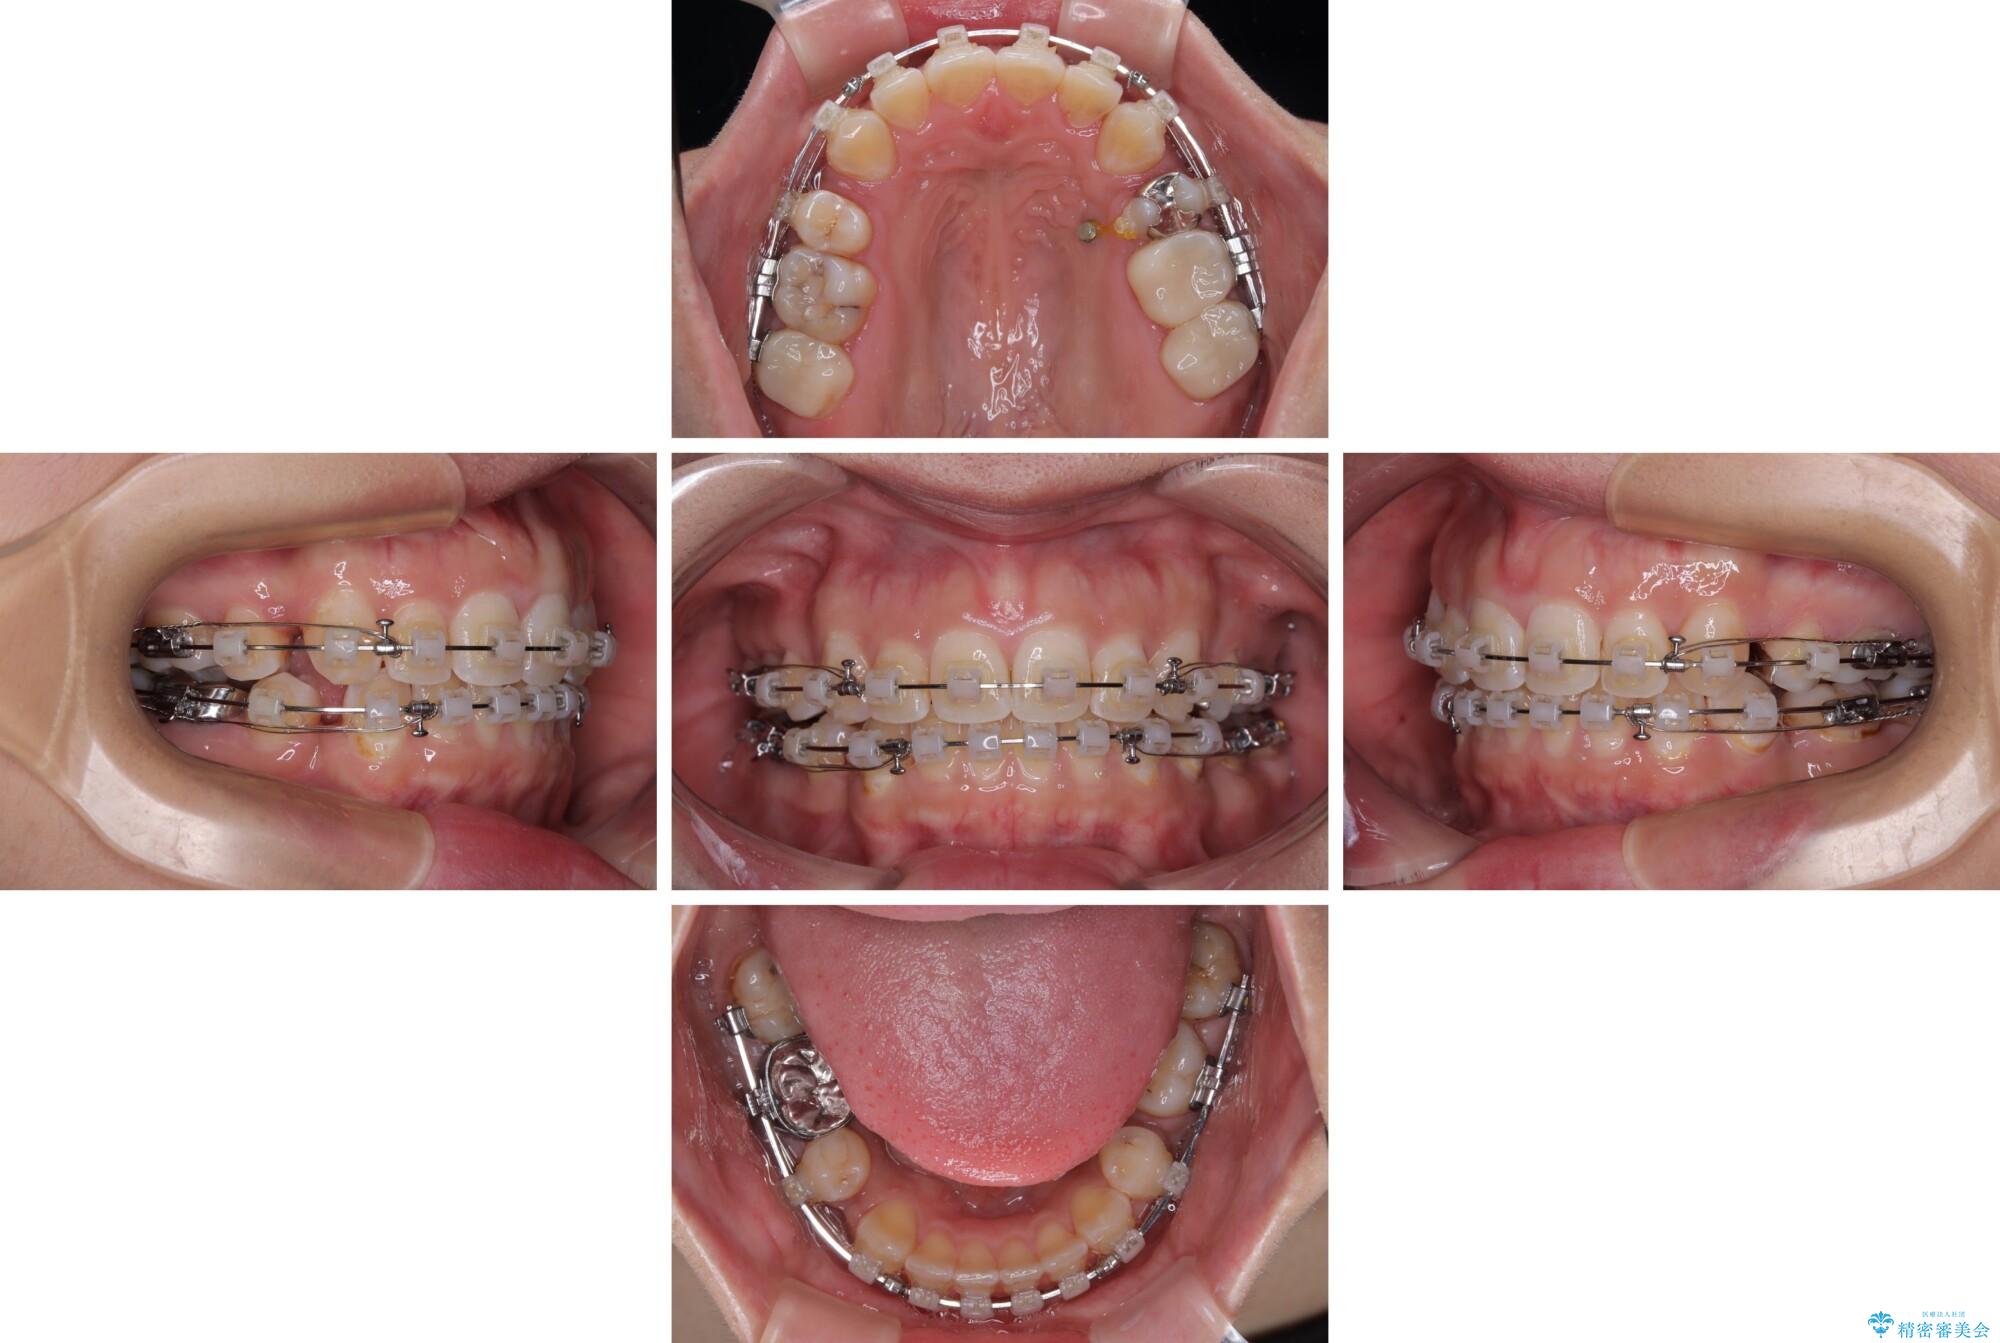

- 矯正装置

- クリアブラケット

- 治療期間

- 2年

第二小臼歯抜歯はイレギュラーな治療手段であり、治療期間が延びる傾向にありますが、予定よりも早い2年間で終えることができました。